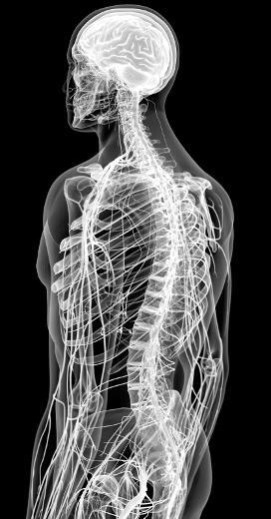

![]() Передние и задние рога серого вещества спинного мозга окружены белым веществом. Белое вещество Белое вещество состоит из пучков миелиновых нервных волокон, которые образуют нервные пути, проходящие вверх и вниз по позвоночнику и соединяющие мозг в обоих направлениях. Восходящие нервные пути направляют сенсорные импульсы в мозг, а нисходящие отправляют двигательные команды в ПНС. Центральный распределитель нервных сигналов Эти волокна нейронов по всей длине спинного мозга объединяются со вставочными нейронами, которые передают сообщения чувствительным или двигательным нейронам. Распознанные организмом ощущения передаются в головной мозг, а эффекторные команды отправляются из мозга в ткани организма. Спинной мозг – это полноценный менеджер среднего звена. Чтобы лишний раз не обращаться к руководству, он сам управляет простыми рефлексами (см. «Рефлексы» на стр. 98–99). Это защищает головной мозг от перегрузки и позволяет ему фокусировать ресурсы на более насущных делах. ![]() Наш спинной мозг отлично поживает внутри костей спины. Анатомия нерва Нерв – это не синоним нейрона, хотя последний и входит в его состав. Нервы состоят из пучков двигательных и чувствительных нейронов, или волокон, а также кровеносных сосудов и соединительной ткани. По своему строению нервы немного похожи на мышцы: они также собираются в пучки, а каждый их внутренний слой выстлан соединительно-тканной прослойкой. Каждое аксональное волокно заключено в слой рыхлой соединительной ткани (эндоневрий). Сами эти волокна объединяются в пучки нервов, и их оборачивает периневрий. Нервный ствол образуют пучки аксональных волокон с кровеносными сосудами, он также покрыт эпиневрием. ![]() Нерв содержит пучки нервных волокон. 43 Соединить центральную нервную систему с остальной частью организма достаточно сложно. Здесь, как и в системе кровообращения, нужна крупная сеть специальных структур, разветвляющихся в каждый сантиметр тела. ПНС делает это с помощью 43 пар нервов. Черепные нервы 12 из 43 пар нервов приходится на черепные нервы. Они отходят от нижней части мозга и иннервируют органы чувств и мышцы головы. Исключение составляет X пара – блуждающий нерв, или вагус, который проходит по телу и соединяет дыхательные пути, сердце и пищеварительную систему. Одни черепные нервы относятся к категории двигательных, другие – чувствительных, а третьи являются и тем, и другим. ![]() Существует 12 пар черепных нервов. Спинно-мозговые нервы 31 пара спинномозговых нервов служит переносчиком как сенсорных, так и моторных сигналов. Эти нервы иннервируют соматические и вегетативные отделы ПНС в областях ниже шеи. Некоторые нервы объединяются, образуя нервную сеть под названием «сплетение». Начиная со второго поясничного нерва и до самого конца позвоночника спинномозговые нервы свободно плавают в СМЖ, образуя пряди, похожие на конский хвост. Их так и называют – конский хвост. ![]() Периферические нервы выходят из спинного мозга. Ветви и корешки Первую часть нерва, выходящего из ЦНС, называют нервным корешком. В основном корешки черепных нервов образуются из ствола головного мозга, за исключением обонятельных и зрительных нервов, которые отходят из головного мозга. Корешки спинномозговых нервов, напротив, отходят от спинного мозга. У них есть двигательные или чувствительные отростки, которые впадают в передние или задние рога серого вещества переднего мозга либо выходят из них. Двигательные (эфферентные) нервы выходят из спинного мозга вертикально – с передней стороны, или антериально. Их чувствительные собратья (афферентные нервы) входят в спинной мозг дорсально – с задней стороны, или постериально. Смешанные спинномозговые нервы появляются, когда вентральные и дорсальные корешки сливаются чуть дальше от спинного мозга. Затем они снова разделяются и образуют ветви, каждая из которых переносит моторные и сенсорные нервные сигналы. Эти нервы продолжают ветвиться, формируя в организме нервную сеть. Ганглии Ганглии – это скопления клеточных тел нейронов, чем-то похожих на ядра в головном мозге. В отличие от мозговых ядер, ганглии рассредоточены по всей площади ПНС. Сенсорные, или корешковые, ганглии располагаются в дорсальных корешках спинномозговых нервов. Вегетативные ганглии (см. «Вегетативные ганглии» на стр. 221) связывают вегетативную и соматическую системы. Для этого они формируют вертикальные цепи, которые с помощью нервных ветвей прикрепляются к спинномозговым нервам. Это автоматика У ПНС есть не только соматическая (телесная) часть, но и вегетативная (автономная), которая помогает телу осуществлять ряд действий (например, дышать) без сознательных усилий с нашей стороны. Вегетативную нервную систему (ВНС) регулирует гипоталамус. ![]() Соматическая часть ПНС состоит из двигательных и чувствительных нервов. Они соединяют головной мозг с органами чувств, которые получают информацию о внешнем мире и позволяют нам осмысленно решать, как лучше отреагировать на происходящее. ВНС состоит из двигательных, или эфферентных, нервов. Обычно эти нервы отходят от спинного мозга, но часть выходит из ствола головного мозга. Эфферентные нервы иннервируют кровеносные сосуды, железы и такие органы, как сердце, легкие, желудок, кишечник, мочевой пузырь и половые органы. Симпатика и парасимпатика Как только гипоталамус получает информацию об изменении, к примеру сердечного ритма или артериального давления, он активирует соответствующие центры в стволе мозга (продолговатый и средний мозг). Мозговые центры стимулируют АНС, чтобы вернуть организм в состояние баланса. В этой обратной цепной реакции задействовано две части АНС – как инь и янь. Симпатическая нервная система готовит нас ко встрече с любыми угрозами и выдает быструю реакцию, помогающую выйти из сложных ситуаций. Парасимпатической нервной системе, наоборот, требуется некоторое время на принятие решений. Можно сказать, что она является стандартным режимом нашего организма, поскольку занимается более рутинными и не угрожающими жизни задачами. Парасимпатика побуждает нас либо «есть и размножаться», либо «отдыхать и переваривать». В реальности отношения между этими двумя системами не столь однозначны. Тем не менее они обе работают на благо баланса и гомеостаза в тех случаях, когда что-то идет не так. |